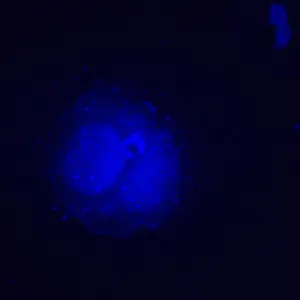

MAGUS Lum V500L – это инвертированный микроскоп для исследований люминесцентным методом в отраженном свете и методами светлого поля и фазового контраста в проходящем свете. Для люминесценции используются фильтры, оптимально подходящие для работы с флюорохромами DAPI, FITC и TRITC. Инвертированная конструкция позволяет изучать образцы в лабораторной посуде – чашках Петри, колбах и проч. Высота посуды может составлять 55 мм, а при отклоненном штативе – 165 мм. Оптика рассчитана на толщину дна посуды 1,2 мм. Микроскоп отлично подходит для исследовательской работы и рутинной лабораторной диагностики, может использоваться для обучения студентов вузов.

В качестве источника возбуждения люминесценции выступает светодиод мощностью 5 Вт и с ресурсом работы 50 000 часов без замены. Фильтров возбуждения три – для флюорохромов DAPI, FITC и TRITC. Светодиодное освещение более экономичное и простое в обслуживании, чем ртутное, поэтому рекомендуется для обучения в вузах. Светодиоды сохраняют постоянство цветовой температуры, быстро включаются и выключаются, не перегреваются при длительной работе.

- Фильтры возбуждения люминесценции для флюорохромов DAPI, FITC и TRITC

| Флуоресцентный модуль | фильтры (флюорохромы): DAPI, FITC, TRITC | |

| Фильтры возбуждения люминесценции: тип фильтра, длина волны возбуждения / дихроичное зеркало / длина волны запирания | DAPI, 365/35 нм / 400 нм / 450/65 нм; FITC, 475/40 нм / 500 нм / 535/45 нм; TRITC, 525/45 нм / 565 нм / 595/60 нм | |